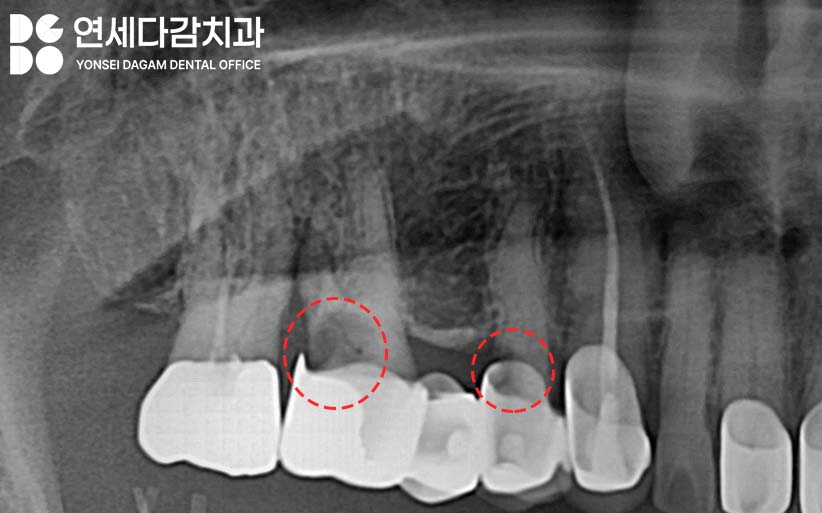

보철 내부는 엑스레이로도

투과되어 보이지 않기 때문에

발견이 어려운 경우가 많습니다.

따라서 주의 깊게 살펴봐야 될 부위는

보철과 잇몸 사이입니다.

가락시장역 치과 에서 표시한 것처럼

이 부위에 충치가 생기거나

치주 질환이 발생하는 경우가 많은데,

겉으로는 범위가 크지 않아도

내부에서는 심각하게 진행될 수 있습니다.